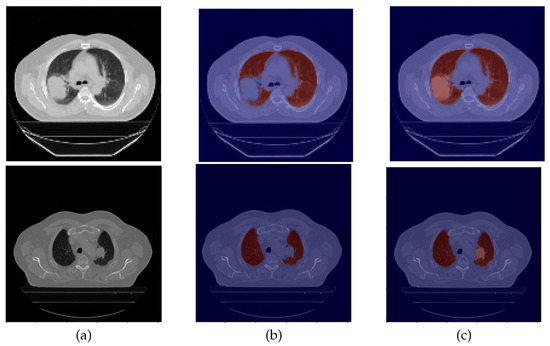

2.2. Mask Segmentation

2.2.1. Original Masks

2.2.2. Mask Correction Protocol